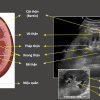

– Cấu tạo thận: xoang thận ở giữa – xung quanh là nhu mô thận (vỏ thận + tủy thận)

+ Xoang thận: chứa mạch máu và thần kinh thận, hệ thống đài bể thận và mô liên kết mỡ. Đài thận nhỏ nhận nước tiểu từ nhú thận, đổ ra đài thận lớn, đài thận lớn hợp thành bể thận – nối với niệu quản.

+ Vỏ thận: nằm ngay dưới bao thận, gồm cột thận (giữa các tháp thận) và các tiểu thùy vỏ từ đáy tháp thận tới bao thận.

+ Tủy thận: do các tháp thận (tháp Malpighi) tạo nên. Đáy tháp thận hướng về phía vỏ thận, đỉnh hướng về phía xoang thận, lồi vào trong xoang thận tạo nên nhú thận – nối với đài thận nhỏ.

=> Siêu âm Doppler: